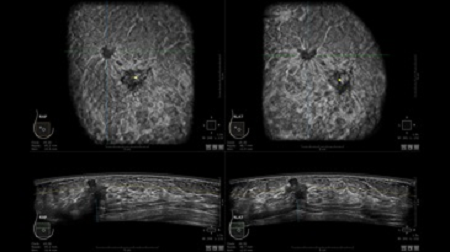

GE INVENIA ABUS – это современный УЗИ аппарат, который создан для точной и эффективной диагностики сканирования с высокой плотностью молочных желез. Выявляемость патологий раковых и предраковых стадий заболевания составляет 55%, что в конечном счете позволяет ставить врачу точные и своевременные диагнозы. Традиционные методы использования маммографии не показывают такой выявляемости, ограничиваясь лишь 3-38%.

УЗИ-аппарат GE INVENIA ABUS позволяет проводить максимально операторонезависимые процедуры, что значительно снижает риск неправильной постановки диагноза и сопутствующие издержки на обработку информации. Система готовит отчет в течение 3-х минут после сканирования, это безусловное преимущество по сравнению с обычным УЗИ сканером.

• Отображение объемных 3D ультразвуковых изображений, которые состоят из традиционных поперечных и воссозданных коронарных и сагиттальных проекций